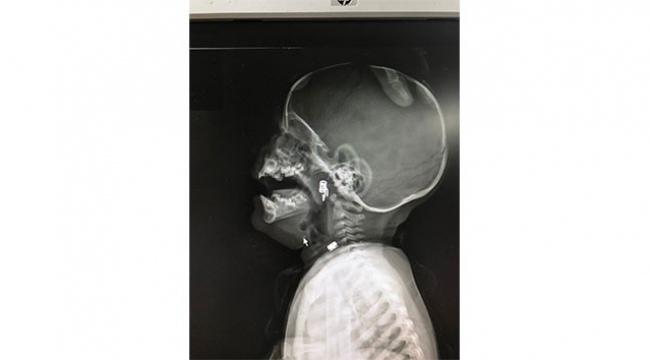

Minik Özlem'in babası ise olayı fark eder fark etmez çocuğunun boğazına kaçan yayı çıkartmaya çalıştı. Daha sonra küçük bebek hastaneye götürüldü. Nöbetçi doktor Dr. Mustafa Alpaslan tarafından bebeğin röntgenleri çekilerek lokalizasyon ve durumu tespit edildi. Daha sonra Kulak Burun Boğaz Uzmanı Op. Dr. Ahmet Cevatzade tarafından da muayene edilen bebeğin acilen ameliyata alınmasına karar verildi. Yapılan başarılı ameliyat sonucunda bebeğin genzin den saplanan mandal yayı çıkartıldı.